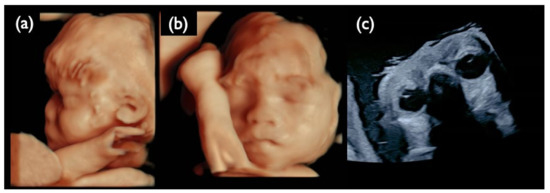

| Chromosome 21 relevant mosaicism | Mo1 | 13 + 3 | XY,+21 Mosaicism | T21 (96%) | 47,XY,+21 (100%) | – | – | T21 positive | 22.05 | + | 4.6 | Increased NT, GE very mild, Micrognathia, Lowset ear, DS like profile, Large VSD, TR moderate, Hyperechoic bowel, DV reverse, Tachycardia, Straight cord, T21 is strongly suspected |

| Mo3 | 13 + 0 | XXY | T21 (2%) | 47,XXY /48,XXY,+21 (62%/38%) | T21 (2%) | 47,XXY | T21 Negative | –0.48 | + | 3.4 | Increased NT, Small NB, TR mild, SUA, Genetic disorder is suspected | |

| NC2 | 12w2d | CVS | 22.8 | 47,XY,+21 | No Call | + | 5.3 | Increased NT, Small CH, GE, bilateral, PE, NB defect, Micrognathia, Lowset ear, s/o Large VSD, TR moderate, Levocardia, RV>LV, Hyperechoic bowel, DV reverse, Short FL, T 21 is strongly suspected |